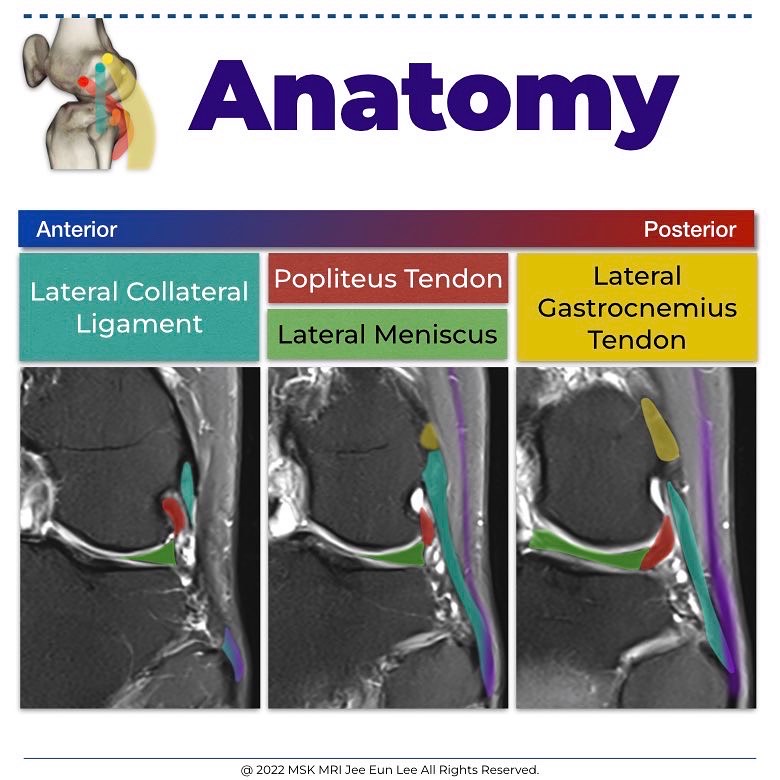

The tendon, which is intracapsular, but extra-articular and extrasynovial, ascends around the posterolateral aspect of the knee

The popliteofibular ligament extends from the popliteus tendon near the myotendinous junction to the posterior aspect of the fibular styloid process, posteromedial to the biceps insertion

- Lateral gastrocnemius tendon

The lateral gastrocnemius tendon becomes adherent to the posterior capsule of the knee at the level of the fabella, and inserts onto the distal femur at the supracondylar process, just posterior to the fibular collateral ligament attachment

- Lateral collateral ligament

The fibular collateral ligament, or lateral collateral ligament, originates from the distal femur in a fanlike fashion between the lateral epicondyle and supracondylar process (attaching just proximal and posterior to the lateral epicondyle), and directly anterior to the lateral head of the gastrocnemius muscle.